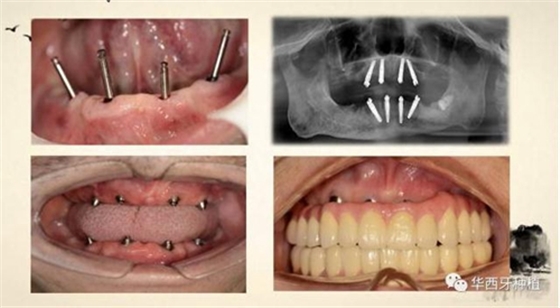

吳教授特別針對手術(shù)難度更大的all-on-four修復(fù)做了詳細的關(guān)于概念、設(shè)計、操作、修復(fù)的描述,首先是針對難度最大的手術(shù)環(huán)節(jié),就解剖、微創(chuàng)操作分別加以闡述。將他自己在臨床工作中的寶貴經(jīng)驗分享給了大家。

對于傳統(tǒng)的all-on-four術(shù)式,吳教授加入了微創(chuàng)的指導思想,設(shè)計時同樣加入數(shù)字化三維重建與修復(fù)一體化設(shè)計,增加了手術(shù)的可控性,同時極大減輕了患者的創(chuàng)傷程度,縮短了修復(fù)周期。

但是,他同時提到了此種修復(fù)方式操作難度要求很高,僅適合有經(jīng)驗的種植醫(yī)生操作。